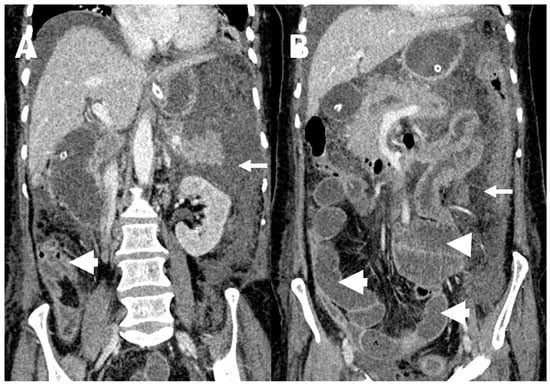

3.4. Peritoneal Involvement

3.5. Predictors of Peritoneal Carcinomatosis